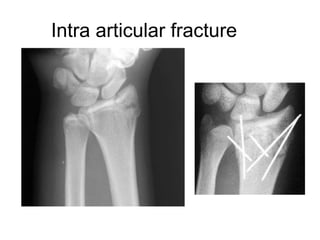

• INTRA ARTICULAR INJECTIONS

Intra-articular injections